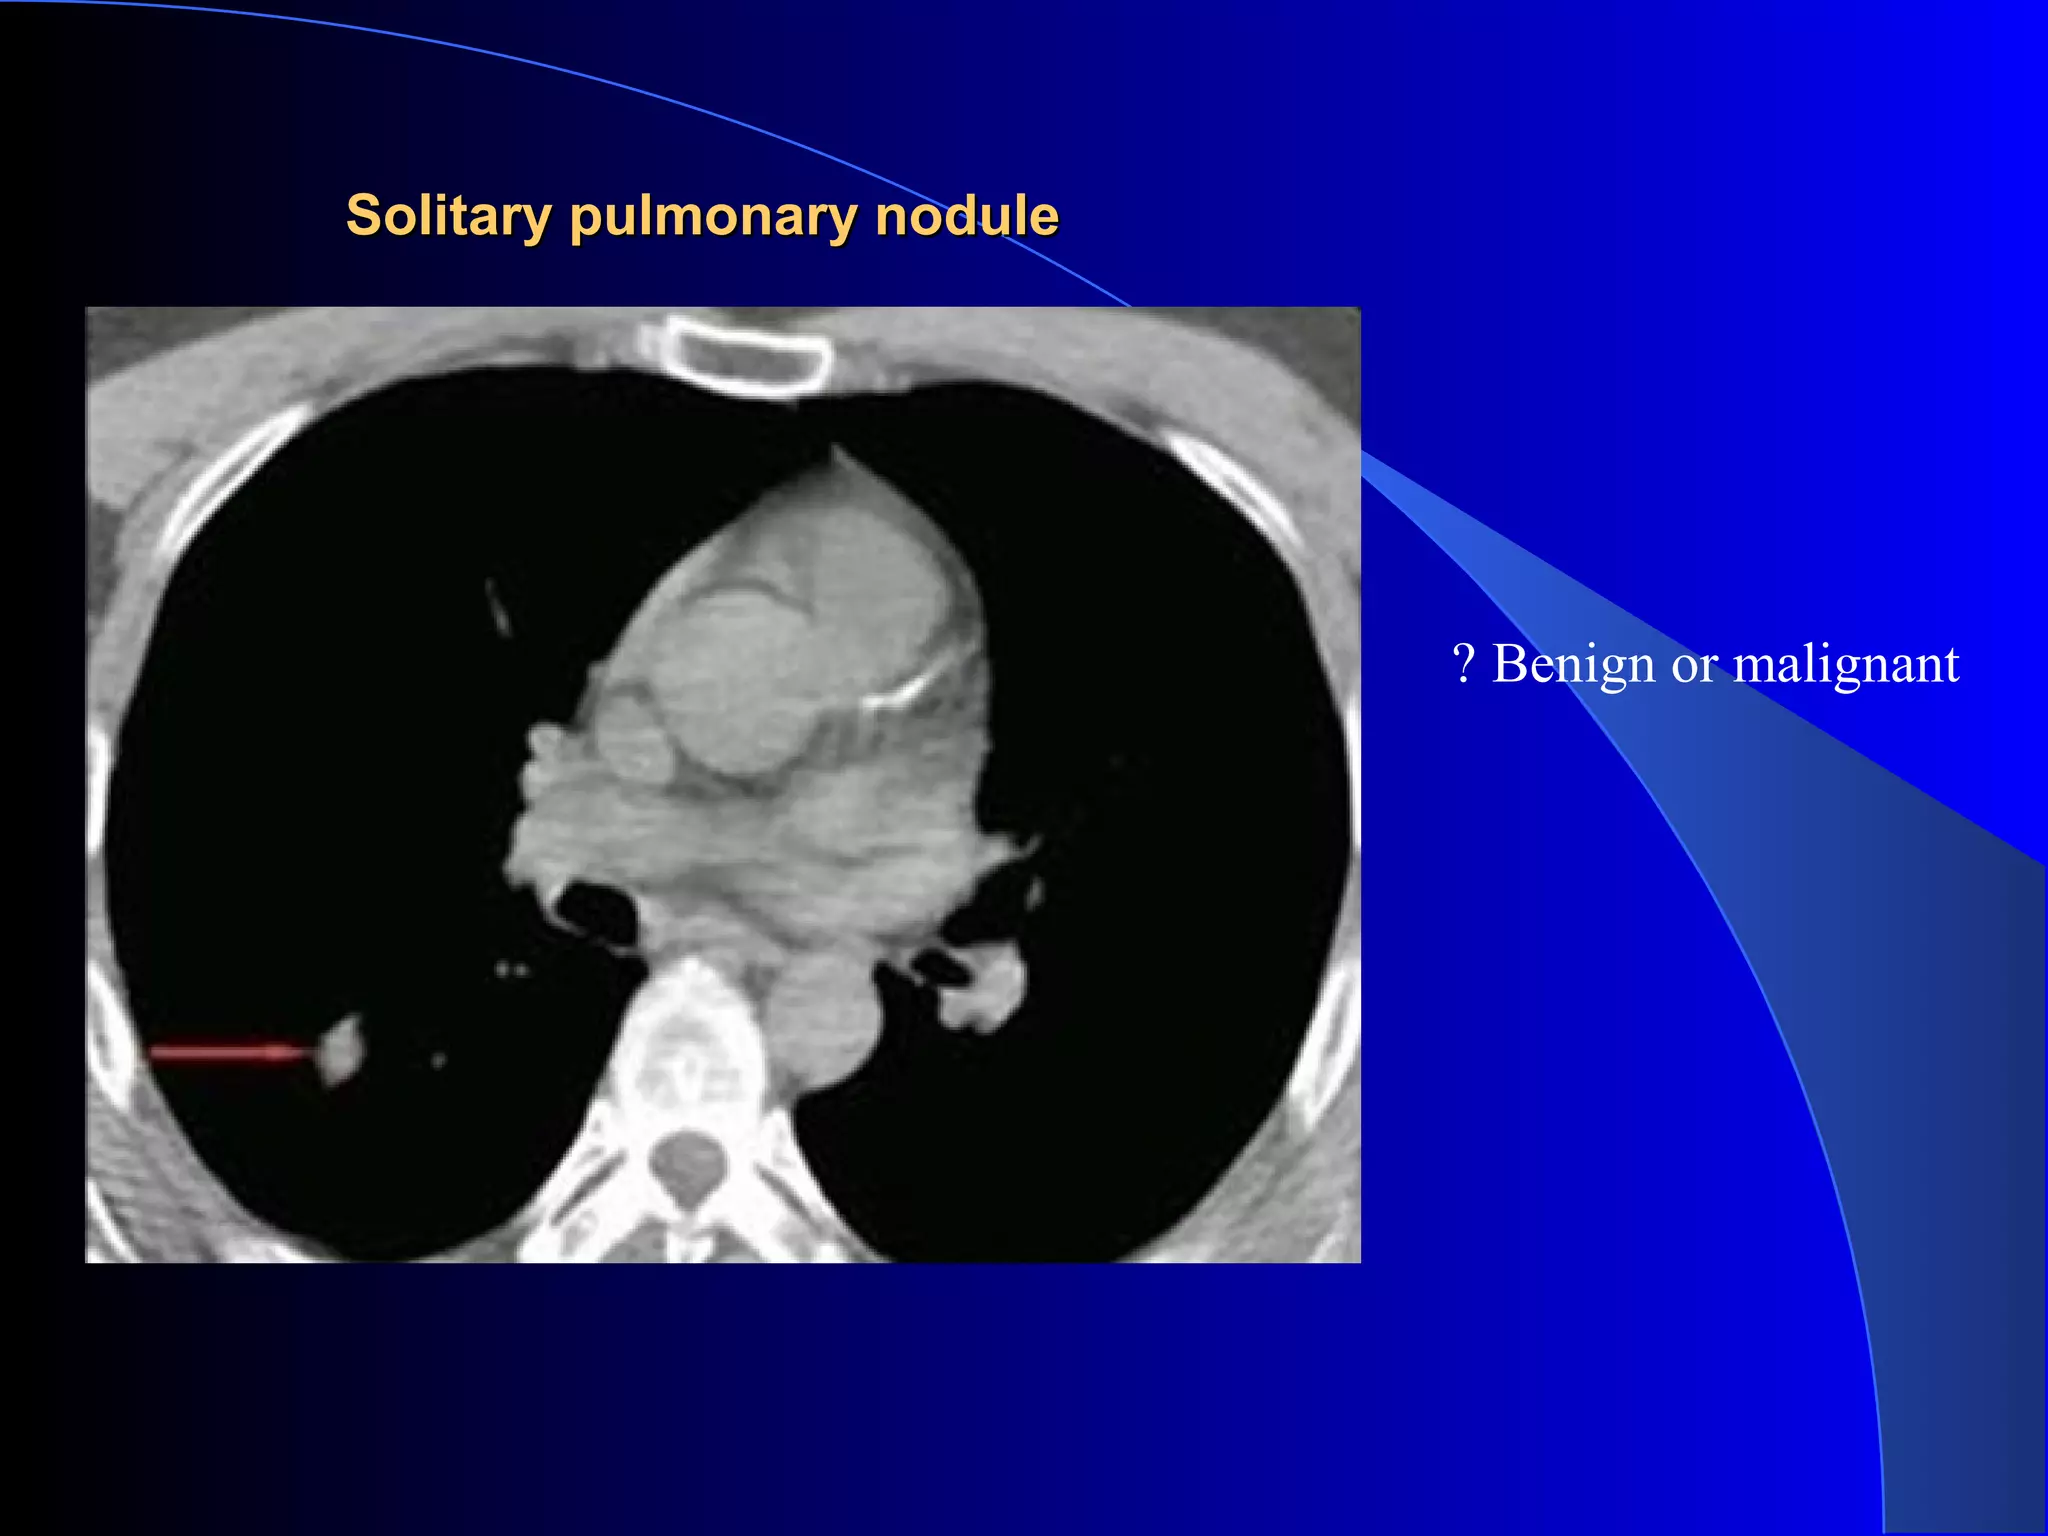

Solitary pulmonary noduleSolitary pulmonary nodule

? Benign or malignant

No activity. Diagnosis: benign bronchocoele

Approximately 85%

of metabolically

active pulmonary

nodules are malignant.

If an FDG positive

pulmonary

nodule is found, it

should be assumed to

be malignant until

proved otherwise.

False positive SPN False negative SPN

1.Granulomas BAC

2.Sarcoidosis Scar adenoca

3.Infection carcinoids

4.Adenomas

5.Hamartomas

6.Neurofibromas